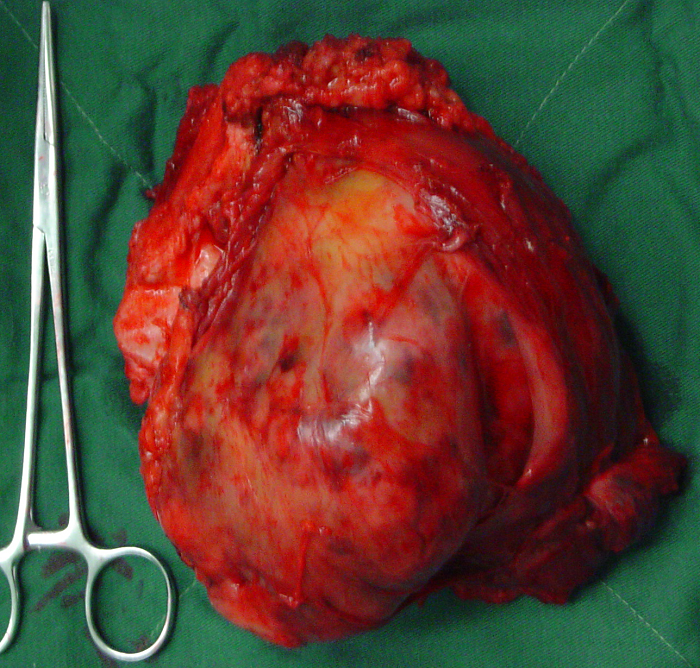

3、病例3:女 25岁 左股骨下端骨旁骨肉瘤,行瘤段广泛切除定制型假体置换术

图 18 肿瘤标本

a:外观象 b:剖面象